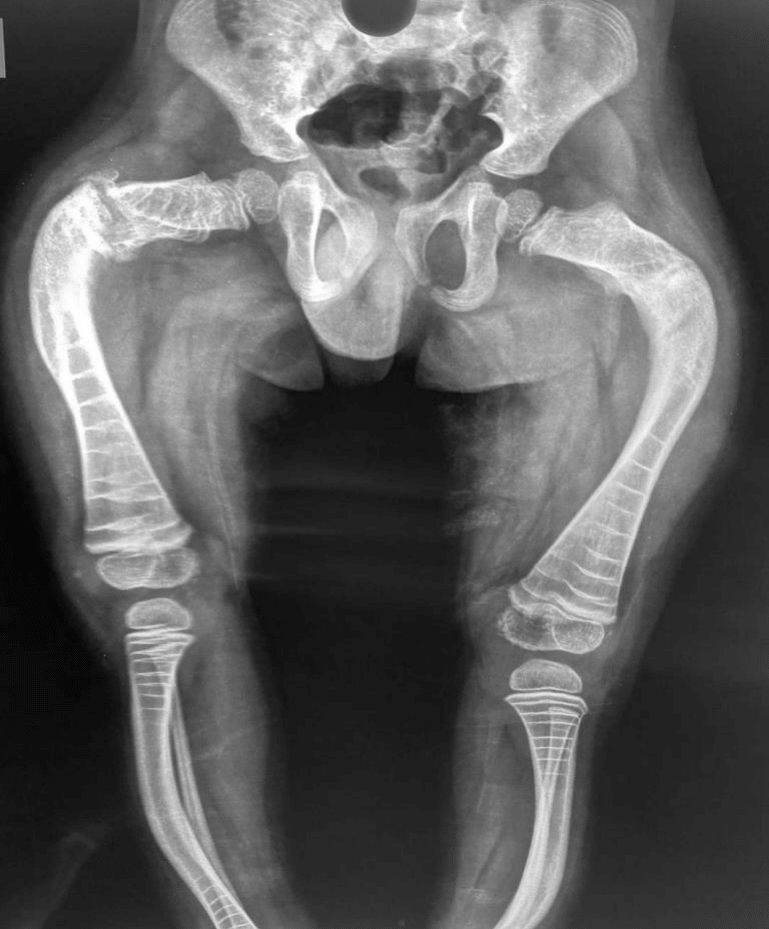

Due to the frequent lower limb fractures and hospital admissions, it was indicated surgical treatment of deformities through osteotomies and fixation with telescopic intramedullary nail. (Figure 1)

Figure 1 Pre-operative X rays where we can see the deformities in anterior and lateral plane of the femur and tíbia.